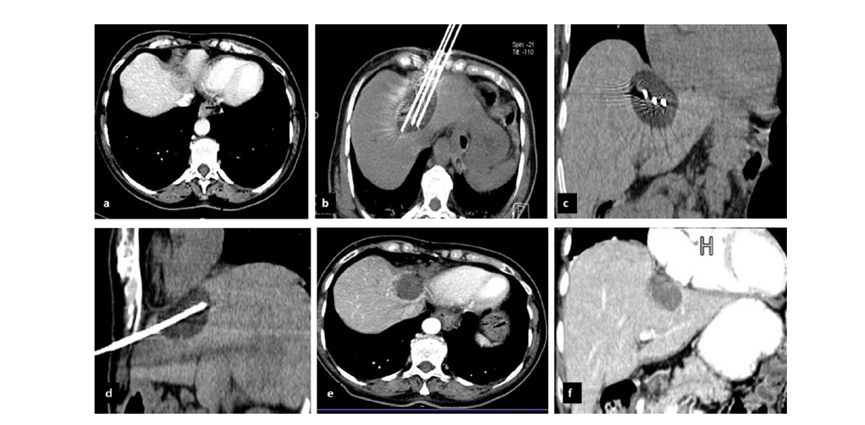

冷凍消融膽囊附近腫瘤病灶

(A)動脈期 MRI 顯示膽囊附近有外周增強病變(箭頭)。

(B)手術過程中 CT 顯示冷凍探針位于病灶內。

(C)消融后,術后 1 個月CT 顯示完全消融(箭頭)。

(A)動脈期CT圖像顯示有一個包膜下結節(箭頭)。(C) 在手術過程中的CT顯示一個冷凍探針位于病灶內。隨訪時間中位數為7個月(范圍:3-12個月),隨訪期間患者無局部腫瘤進展或死亡。

(A)門靜脈期 CT 圖像顯示膽囊附近有病變(箭頭)。(D)消融手術后 1 個月CT 顯示完全消融。

CT引導的冷凍消融